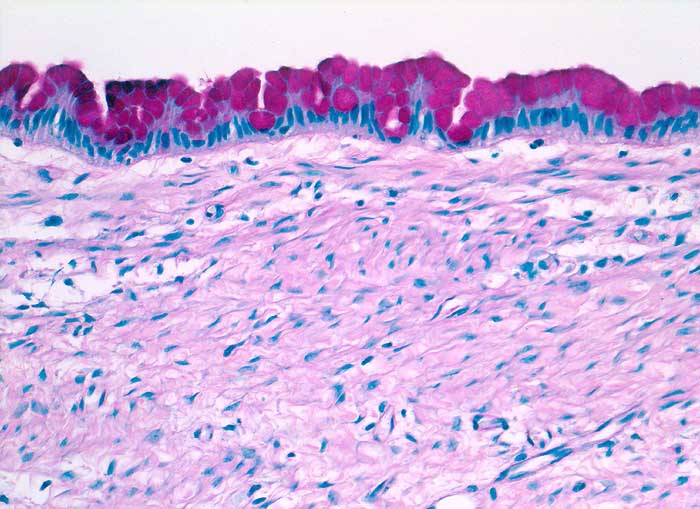

Die gut erkennbaren Zellgrenzen der hohen schlanken Zylinderzellen bilden bei Aufsicht ein Honigwabenmuster. Das Zytoplasma enthält eine grössere oder mehrere kleine apikale Schleimvakuolen, die den Zellkern zur Seite drängen. Das Chromatin ist fein granulär und regelmässig verteilt. Der Nachweis von Schleimbildung schliesst eine funktionelle Zyste aus. Metastasen von schleimbildenden Adenokarzinomen zeigen eine stärkere Kernpolymorphie und bilden keine regelmässigen Verbände.